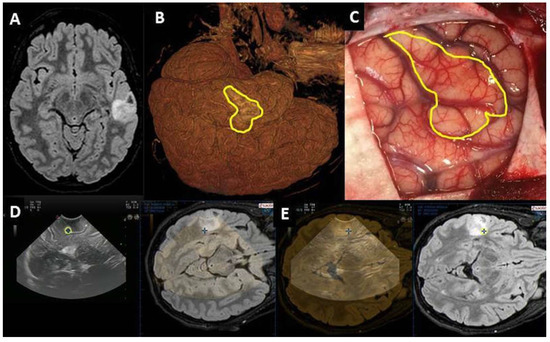

| Post-IOUS | ||

| EOR | Collapsed surgical cavity |

|

| EOR | Open ventricle |

| EOR | Artifacts |